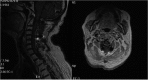

We report a case of a giant intra and extradural cervical schwannoma in a patient affected by a severe myelo-radiculopathy. Clinical features, diagnosis and the issues concerning the surgical management of this benign tumor are discussed. We also review similar cases previously reported in the literature. A 50-year old caucasian woman was complaining of a 1 year of neck pain and worsening motor impairment in all four limbs causing the inability to walk. Neuroradiological assessment revealed a suspected schwannoma involving the nerve roots from C3 to C5, compressing and deviating the spinal cord. The vertebral artery was also encased within the lesion, but still patent. A posterior cervical laminectomy with a microsurgical extradural resection of the lesion was performed. Moreover, an accurate dissection of the lesion from the vertebral artery and the resection of the intraspinal component was achieved. Vertebral fixation with screws on the lateral masses of C3, C5 and C6 and a hook on C1 was performed. The procedure was secured using electroneurophysiological monitoring. A progressive improvement of the motor functions was achieved. A cervical post-contrast MRI revealed optimal medullary decompression and a gross-total resection of the lesion. Schwannomas are benign, slowly growing lesions which may cause serious neurological deficit. Early diagnosis is necessary and it maybe aided by imaging studies such as MRI or CT. The accepted treatment for these tumors is surgical resection and, when indicated, vertebral fixation.